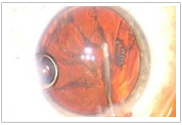

在整個(gè)治療、計(jì)劃和手術(shù)過(guò)程中,可提供整個(gè)眼前節(jié)的三維圖像。

手術(shù)醫(yī)生可以在手術(shù)過(guò)程中監(jiān)視全部眼前節(jié)

(1)高分辨率的視頻顯微鏡,實(shí)時(shí)成像

(2)一體化的、廣角的光學(xué)相干斷層

掃描(OCT),三維成像